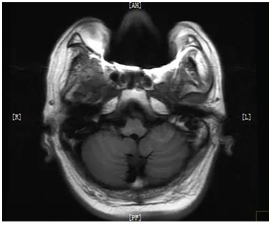

??磁共振检查没有创伤、无辐射,组织分辨率高、图像更清晰,可帮助医生看见不易察觉的早期病变,被广泛应用于脑部、心脏、大血管、脊髓、脊椎、关节等多种临床病变的诊断。